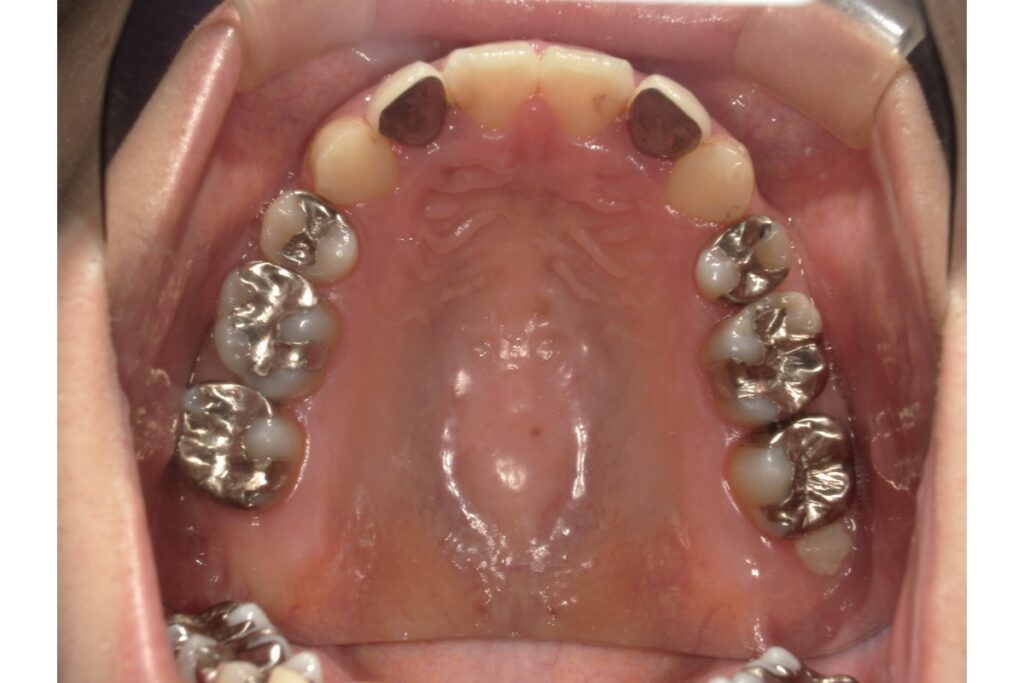

医院ブログ 2025/07/19【歯列矯正】被せ物がたくさん入っていても矯正治療はできる?